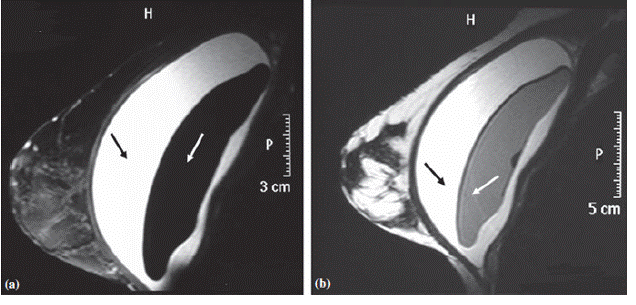

Капсуларная контрактура является наиболее частым осложнением в отдаленном послеоперационном периоде после установки имплантов. При нормальных темпах заживлении (см. нормальное заживление тканей тут) раны тонкий слой соединительной ткани вокруг импланта образуется уже через 4-6 недель после операции. Образование капсулы является физиологической реакцией на наличие инородного тела. При идеальном стечении обстоятельств толщина капсулы минимальна, капсула полностью повторяет анатомическую форму имплантат и не пальпируется. Тем не менее, достаточно часто капсула может сжиматься, сдавливая имплант, что приводит к появлению субъективных неприятных ощущений. Согласно Baker, принято выделять 4 степени сжатия импланта. При 1 степени молочная железа имеет мягкую консистенцию, имплант не пальпируется. При 2 степени характерными являются незначительно выраженные пальпаторнэ признаки капсулы. При 3 степени имплант четко визуализируется и имеет пальпаторно уплотнение тканей в области импланта. Для 4 степени характерно присоединение достаточно выраженного болевого синдрома. Сжимание капсулы может развиваться как в раннем п/о периоде, так и спустя несколько лет после операции. При постановке импланта с обеих сторон может иметь место двусторонний характер патологических проявлении. При незначительной выраженности процессов контракции (1-2 степень) пациенты могут н предъявлять никаких жалоб (вплоть до полного отсутствия симптоматики). Для 4 стадии характерно ощущение инородного тела и хронический болевой синдром.

Клинические исследования в достаточно продолжительном периоде показали, что контракция наступает в 4-5% случаев в течение 10 лет после установки имплантов. Частота данного осложнения увеличивается до 10-15% в течение 20-летнего периода, и до 20-25% в течение 30 после операции.

Для сравнения, уплотнение молочной железы в течение 2 лет после выполненных реконструктивных операциях встречаетсыа у 30-35%.

При контракциях капсулы, для коррекции показаны повторные хирургические вмешательства, а именно капсулотомия. Иногда может также потребоваться замена имплантов. Капсулотомия проводится открытым методом под визуальным контролем хирурга, для предотвращения повреждения импланта.